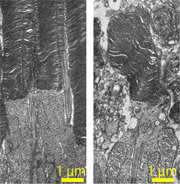

また、魚に多く含まれることで知られる脂肪酸、DHAを膜に取り込む酵素を発見し、これを欠損したマウスをつくるとオスが不妊になることを見つけました。DHAは精巣に多く含まれており、DHAが不足すると生殖機能に異常が出ることは知られていましたが、その分子機構がわかり始めたのです。またこの酵素の欠損で網膜変性も起きます。網膜にもDHAが非常にたくさん含まれていることから、おそらくDHAの持つ柔軟な膜構造が、視細胞の構造を保つのに重要なのではないかと考えているのですが、まだはっきりしていません。今、膜の化学的性質だけでなく、硬さや流動性などの物理的性質も見ていこうとしているところです。

マウス網膜の視細胞の比較。正常なマウスの視細胞(左)と比べ、DHAが欠損した視細胞(右)は形が崩れていることがわかった。DHAは脂質膜の柔らかさに影響を与える脂肪酸だが、細胞の形の維持に重要な役割を果たしているようだ。(出典:Docosahexaenoic acid preserves visual function by maintaining correct disc morphology in retinal photoreceptor cells. Shindou et al. (2017) J. Biol. Chem. ;292 (29)より)

マウス精子の比較。正常なマウスの精子(左)に比べ、DHAが欠損した精子(右)は頭部に余分な物質が付着し、先端が折れ曲がっている。膜の性質の変化を介した精子の変化が、不妊につながるようだ。(出典:Lysophosphatidic acid acyltransferase 3 tunes the membrane status of germ cells by incorporating docosahexaenoic acid during spermatogenesis. Iizuka-Hishikawa et al. (2017) J. Biol. Chem. ;292 (29)より)